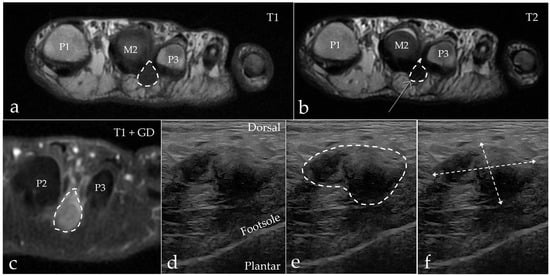

3.2. Imaging Results